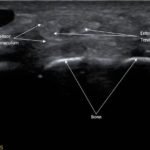

Point-of-care ultrasound of the dorsal aspect of the left hand reveals a heterogenous hypoechoic fluid collection surrounding the extensor tendons (axial view) within the retinaculum consistent with edema. Longitudinal view shows anechoic fluid within the tenosynovium which is located between the anisotropic extensor tendon and linear hyperechoic synovial sheath. Longitudinal view also shows some cobblestoning, or tissue edema, superficial to the anisotropic extensor tendon. The patient’s contralateral right dorsal hand was scanned in a longitudinal view and shows no cobblestoning or hypoechoic fluid under the synovial sheath. The patient was diagnosed with tenosynovitis, and started on intravenous antibiotics.

There is a paucity of literature on extensor tenosynovitis compared with flexor tenosynovitis. The diagnosis of tenosynovitis of the wrist is often clinical using Kanavel’s cardinal signs developed in 1912, though this was developed for flexor, and not extensor tenosynovitis.1 More recently, ultrasound has been used to diagnose tenosynovitis with a sensitivity of 94% and has been shown to be more sensitive than clinical exam.4,5,6 Ultrasound findings may include hypoechoic to anechoic fluid and cobblestoning of the soft tissues, a thickened tendon sheath, and abnormal hypoechoic material within the synovial sheath.5 These ultrasound findings are best seen using a high frequency linear probe oriented in the transverse and longitudinal planes over the dorsal aspect of the hand.6 Our patient’s ultrasound demonstrated cobblestoning of the soft tissues and abnormal hypoechoic material within the synovial sheath; however, we did not measure synovial sheath thickness. While superficial cobblestoning is commonly seen in cellulitis, a thickened synovial sheath and/or abnormal hypoechoic material within the synovial sheath should prompt consideration of tenosynovitis.